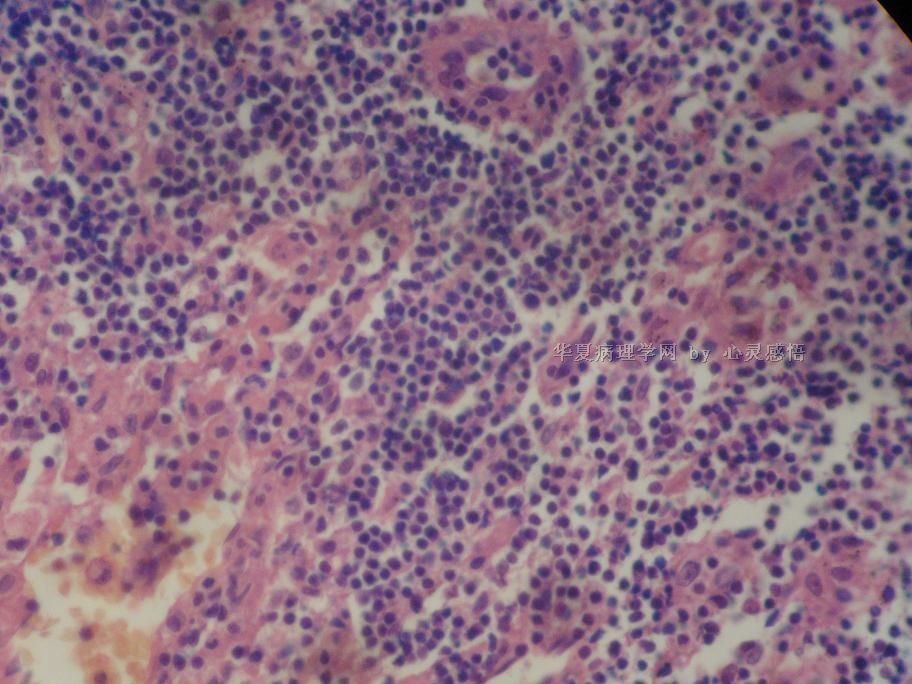

• 食道癌,淋巴结有没有转移,谢谢。图2

图2

1-6图是鳞癌。7-22图片无癌。

淋巴结没有转移

本帖最后由 于 2010-11-17 20:19:00 编辑  图14,19有转移

没有转移。

没有转移,食道旁的淋巴结和肺旁的淋巴结相似,含有吞噬细胞。